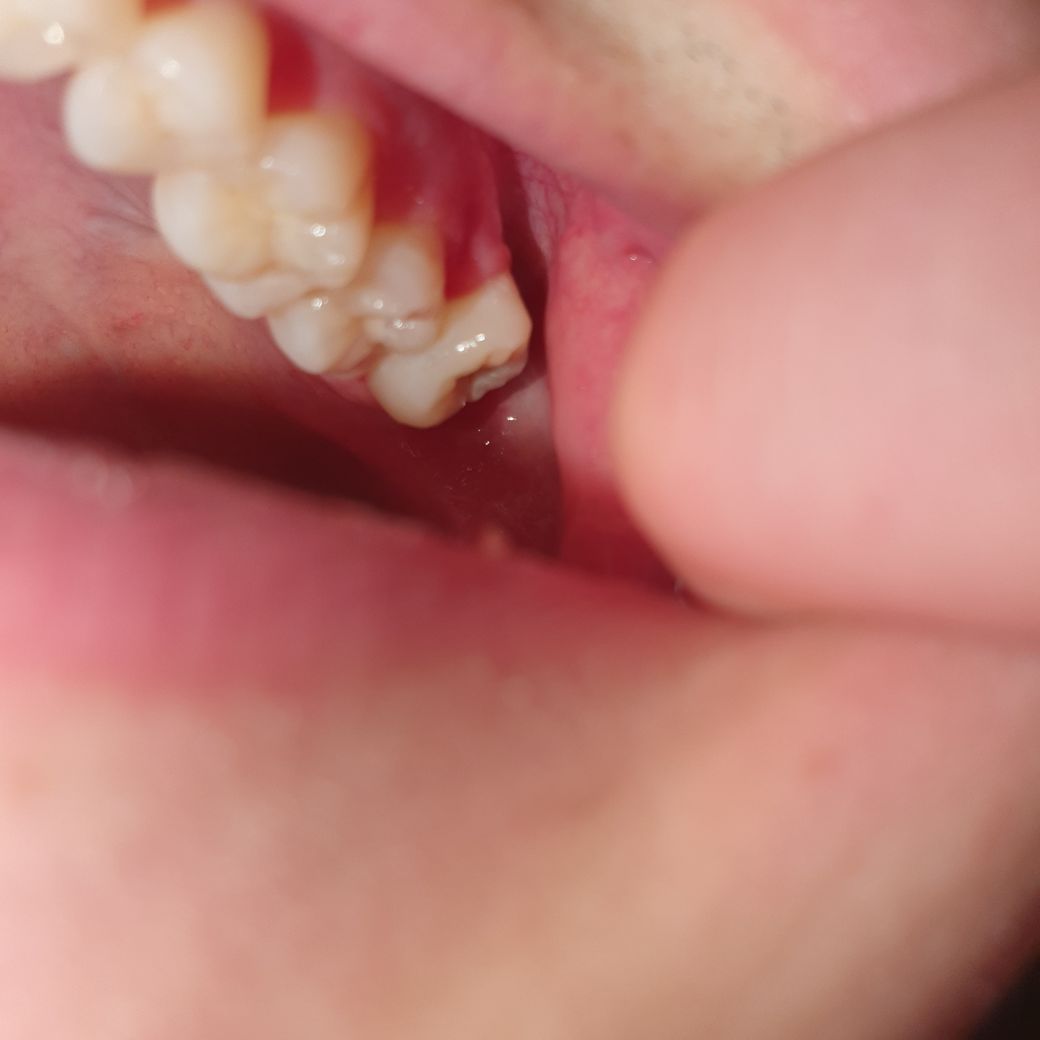

먼저 불편한 사진 왼쪽에 ? 위쪽 사랑니는 음식물이 끼고 잇몸안에 좀 묻혀있어서

제가 동그라미 친게 제 오른쪽 치아인지 모르겠는데

저기는 나름 다 나와있는거 같은데 혹시 이런 경우에 마취 안하고 뽑는 경우도 있나요?